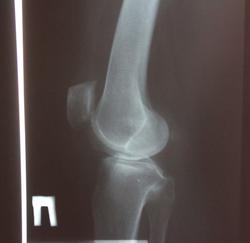

Пол пациента: Мужской пол Тип патологии: Другое Область исследования: Скелетно-мышечная система Методы исследования: Rg Гонартроз.Степень? https://radiomed.ru/sites/default/files/styles/case_slider_image/public/user/17208/img_1016.jpg?itok=h8mkxSs_ ID:24101 Ср, 31/10/2012 - 16:13 #1 фади 79 Не на сайте Был на сайте: 9 лет 2 недели назад Зарегистрирован: 30.10.2012 - 21:15 Публикации: 50 2 Ср, 31/10/2012 - 16:25 #2 Катенёв Валенти... Не на сайте Был на сайте: 7 лет 5 месяцев назад Зарегистрирован: 22.03.2008 - 22:15 Публикации: 54876 фади 79 wrote: 2 Что означает цифра "2"? Ср, 31/10/2012 - 16:50 #3 фади 79 Не на сайте Был на сайте: 9 лет 2 недели назад Зарегистрирован: 30.10.2012 - 21:15 Публикации: 50 второй степень Ср, 31/10/2012 - 17:00 #4 Катенёв Валенти... Не на сайте Был на сайте: 7 лет 5 месяцев назад Зарегистрирован: 22.03.2008 - 22:15 Публикации: 54876 фади 79 wrote: второй степень Второй степени нет, есть второя стадия по классификации Н.С. Косинской. Ср, 31/10/2012 - 17:02 #5 Катенёв Валенти... Не на сайте Был на сайте: 7 лет 5 месяцев назад Зарегистрирован: 22.03.2008 - 22:15 Публикации: 54876 Тут, даже при желании, больше первой нарыть не возможно с учетом таких краеугольных признаков, как субхондральный склероз и краевое остеофитообразование. Ср, 31/10/2012 - 17:04 #6 фади 79 Не на сайте Был на сайте: 9 лет 2 недели назад Зарегистрирован: 30.10.2012 - 21:15 Публикации: 50 А перый , второй? Ср, 31/10/2012 - 20:35 #7 maker4ik Не на сайте Был на сайте: 8 лет 11 месяцев назад Зарегистрирован: 19.10.2011 - 17:49 Публикации: 2682 1-2 Ср, 31/10/2012 - 20:51 #8 Катенёв Валенти... Не на сайте Был на сайте: 7 лет 5 месяцев назад Зарегистрирован: 22.03.2008 - 22:15 Публикации: 54876 Интересно, а почему маячит вторая? Чт, 01/11/2012 - 20:55 #9 maker4ik Не на сайте Был на сайте: 8 лет 11 месяцев назад Зарегистрирован: 19.10.2011 - 17:49 Публикации: 2682 Катенёв Валентин Львович wrote: Интересно, а почему маячит вторая? Щель медиально узковата, в верхнем полюсе надколенника (у нас принято и его учитывать) - остеофит огромный. Но на полноценную 2 все это не тянет. Чт, 01/11/2012 - 21:21 #10 Катенёв Валенти... Не на сайте Был на сайте: 7 лет 5 месяцев назад Зарегистрирован: 22.03.2008 - 22:15 Публикации: 54876 maker4ik wrote: Щель медиально узковата, в верхнем полюсе надколенника (у нас принято и его учитывать) - остеофит огромный. Но на полноценную 2 все это не тянет. Для второй сужение должно быть более 50% Чт, 01/11/2012 - 22:05 #11 алкс Не на сайте Был на сайте: 10 лет 5 месяцев назад Зарегистрирован: 24.10.2012 - 22:55 Публикации: 2915 Катенёв Валентин Львович wrote: maker4ik wrote: Щель медиально узковата, в верхнем полюсе надколенника (у нас принято и его учитывать) - остеофит огромный. Но на полноценную 2 все это не тянет. Для второй сужение должно быть более 50% А если остеофит в малоберцовой? Т.е. учитываете пожалуйста то, что относится к суставу см. пост Катенёв В.Л. Чт, 01/11/2012 - 23:19 #12 Катенёв Валенти... Не на сайте Был на сайте: 7 лет 5 месяцев назад Зарегистрирован: 22.03.2008 - 22:15 Публикации: 54876 Обработанные снимки.Приложения:

Тут, даже при желании, больше первой нарыть не возможно с учетом таких краеугольных признаков, как субхондральный склероз и краевое остеофитообразование.

Щель медиально узковата, в верхнем полюсе надколенника (у нас принято и его учитывать) - остеофит огромный. Но на полноценную 2 все это не тянет.

Для второй сужение должно быть более 50%